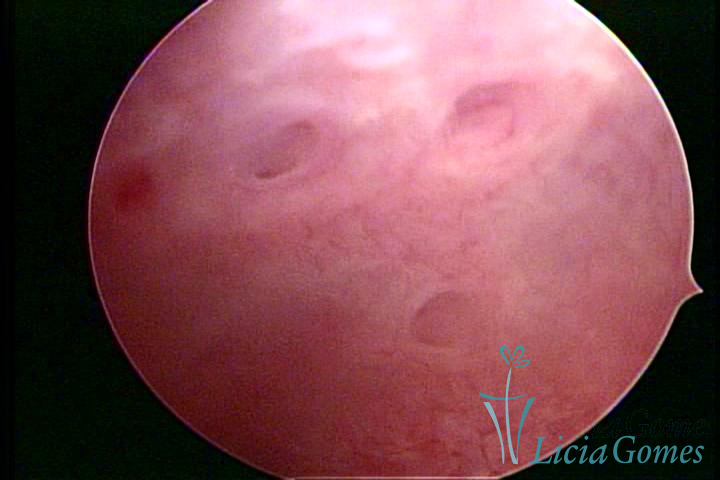

ADENOMIOSE

É a presença de tecido endometrial na camada muscular do útero

A vídeo-histeroscopia permite diagnosticar às lesões próximas às camadas miometriais superficiais, próximo ao endométrio visualizando lesões de coloração violácea, circunscritas, ou acastanhadas com conteúdo achocolatado.